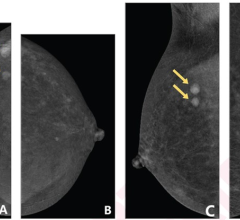

July 13, 2023 — According to an accepted manuscript published in the American Journal of Roentgenology (AJR), a synoptic ...

Despite decades of progress in breast imaging, one challenge continues to test even the most skilled radiologists ...